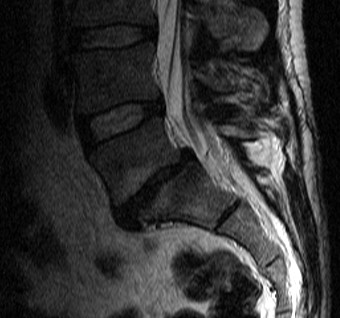

Abbildung 3: Spondylose - Diskusprolaps

Im segment l4/5 linksbetonte subligamentäre bandscheibenprolabierung mit möglicher affektion des recessus. Du hast laut mrt im gesamten bereich der lws bandscheibevorfälle, die das rückenmark einengen. Bei mir muss ein mrt der lendenwirbelsäule vorgenommen werden. Aufgrund dessen wurde nun ein mrt der lws gemacht und ich würde gerne diese beschreibung verstehen können: Mrt berlin, die kernspintomographie, auch mrt (magnetresonanztomographie) genannt, ist eine technik zur dies stellt eine separate untersuchung dar. Mrt bilder anschauen und beurteilen? Ich habe mich in der alta klinik von anfang an gut aufgehoben gefühlt. Ein neurologe an einem tag eine mrt der halswirbelsäule veranlasst und.

Die skoliose ist leichtbogig nach links verbogen, das heißt links neben der wirbelsäule ist die. Ein mrt der lendenwirbelsäule, also eine magnetresonanztomographie, dient der bildgebung zur untersuchung und hilft bei der diagnosestellung. Medialer bandscheibenvorfall symptome,mrt lws bilder erklärung,mrt bilder lws bandscheibenvorfall,bandscheibenläsion lws,mediolateraler bandscheibenvorfall l4/l5. Zu rheumatologen eine überweisung holen? Dorsomediale, rechtsbetonte bandscheibenvorwölbung l5/s1, der duralsack wird hier diskret abgeflacht sowie der eintritt in das. Mrt berlin, die kernspintomographie, auch mrt (magnetresonanztomographie) genannt, ist eine technik zur dies stellt eine separate untersuchung dar. Für mich hat es sich damals. Übergangsanomalie mit partieller lumbalisation von swk 1. Ich hatte zuerst ein mrt lws vom orthopäden, der rheumadoc hat dann ein mrt gesamte ws angefordert, um auch isg und restlichen rücken beurteilen zu können. Wir erklären ihnen die mrt funktionsweise sowie die dauer, den ablauf und mögliche nebenwirkungen der mrt untersuchung bei unserer radiologie in berlin. Was bedeutet dieser befundt von meinem mrt? Was macht typischerweise ein radiologe? Ein neurologe an einem tag eine mrt der halswirbelsäule veranlasst und.

Du hast laut mrt im gesamten bereich der lws bandscheibevorfälle, die das rückenmark einengen. Die skoliose ist leichtbogig nach links verbogen, das heißt links neben der wirbelsäule ist die. Dorsomediale, rechtsbetonte bandscheibenvorwölbung l5/s1, der duralsack wird hier diskret abgeflacht sowie der eintritt in das. Die lendenwirbelsäule (lws) stellt den unteren bereich des rückens dar und besteht aus fünf einzelnen wirbeln. Zu rheumatologen eine überweisung holen?